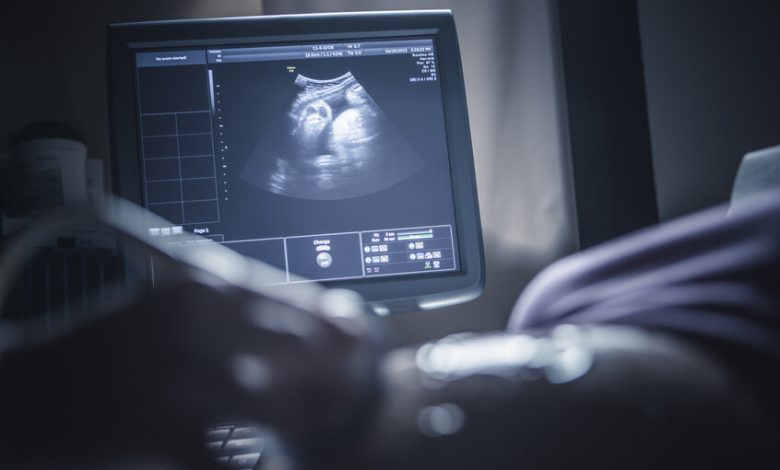

وجدت دراسة حديثة علاقة مقلقة بين تعرض #الحوامل لتلوث #الهواء وتباطؤ عملية نضج #الدماغ لدى #الأطفال حديثي الولادة.

واعتمدت الدراسة على متابعة مجموعة من الحوامل في ثلاثة مستشفيات كبرى في برشلونة، وخضع 132 طفلا حديث الولادة لفحوصات متقدمة بالرنين المغناطيسي خلال الشهر الأول لتقييم مستوى نضج أدمغتهم عبر قياس تقدم عملية الميالينة.